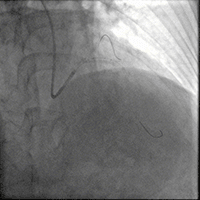

造影如下

患者左主干前三叉1,0,1型病变,主干末端偏心40%狭窄;前降支病变自开口延续至中段,口部80%狭窄,中段80%狭窄,病变位置钙化严重;回旋支近段约30%轻度狭窄,第一及第二钝缘支开口80%局限病变。